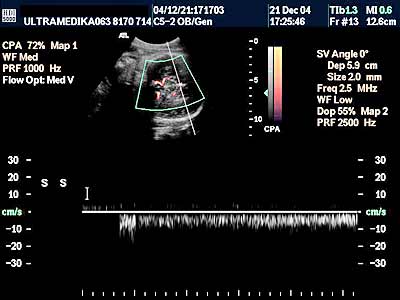

1. Arahnoidalne ciste ne bi trebalo da predstavljaju dijagnostički problem. One su avaskularne te se kolor Dopplerom (CD) ne dobija protok u njima. Ako postoji dilema koristi se kolor Power angio mod (CPA) (sl 010) koji registruje i protoke ekstremno malih brzina bez obzira na upadni ugao ultrazvučnog talasa u odnosu na krvni sud, što je osnovni preduslov za registrovanje protoka krvi, od pre 20 gidina poznatim konvencionalnim kolor Dopplerom . Mora se napomenuti da u toku pregleda u III trimestru trudnoće, jako često postoje nepovoljni uslovi za pregled (neadekvatan položaj ploda, neoptimalna količina plodove vode, debljina prednjeg trbušnog zida trudnice i položaj posteljice). U ovakvim situacijama aparati slabijih tehničkih mogućnosti, sa nižom cenom koštanja i posedovanjem klasičnog načina dobijanja ultrazvučne slike i kolor Doppler tehnike, imaju znatno ograničene dijagnostičke mogućnosti.